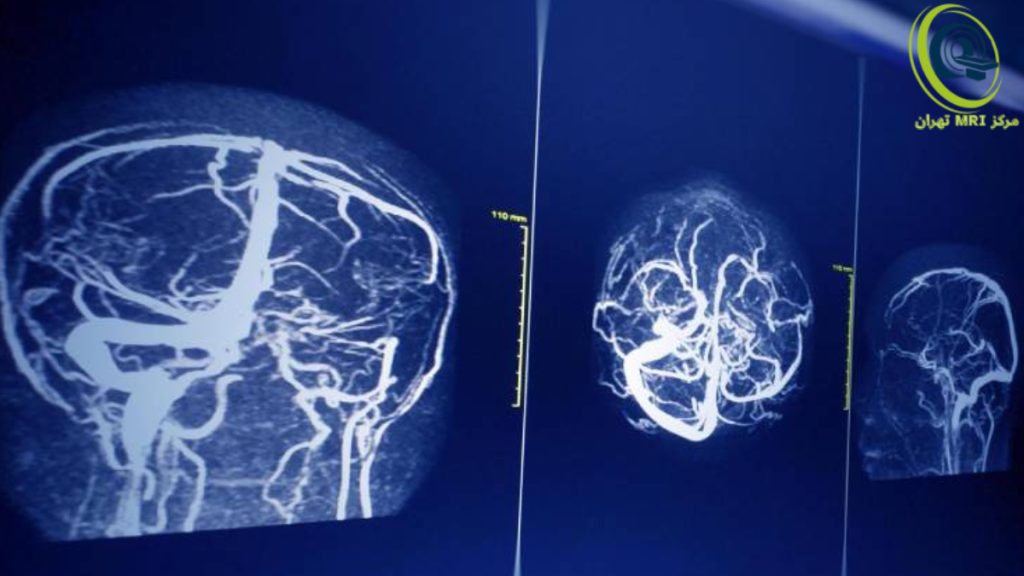

ام آر آی مغز چیست و چگونه انجام می شود؟

این اسکن دقیقترین روش برای بررسی آناتومی مغز است.

- نحوه انجام: سر بیمار داخل یک کویل مخصوص (شبیه کلاه ایمنی شبکهای) قرار میگیرد. این کویل به عنوان آنتن عمل میکند. دستگاه صداهای کوبشی بلندی تولید میکند، بنابراین به بیمار گوشی محافظ داده میشود.

- موارد تشخیص: سکته مغزی (به ویژه در ساعات اولیه)، بیماری اماس (MS)، تومورهای مغزی، آنوریسمها، اختلالات غده هیپوفیز، و عفونتهای مغزی مانند مننژیت. تصاویر در برشهای مختلف (محوری، تاجی و سهمی) تهیه میشوند.

تصویربرداری رزونانس مغناطیسی (MRI) حساسترین روش برای تشخیص تومورهای هیپوفیز و تعیین اندازه آنها است. MRI همراه با تزریق ماده حاجب، حساسیتی در حدود ۹۰٪ دارد. یافتههای مطرحکننده پرولاکتینوما در تصاویر MRI شامل موارد زیر است:

- ضایعه در تصاویر T1-weighted همسیگنال (Isointense) با هیپوفیز طبیعی دیده میشود.

- در سکانسهای دینامیک پس از تزریق گادولینیوم، یک ناحیه گرد با افزایش تأخیری ماده حاجب نسبت به بافت باقیمانده غده هیپوفیز مشاهده میشود.

- در تصاویر تأخیری پس از تزریق گادولینیوم، ظاهر ضایعه متغیر است؛ اما شایعترین حالت، کاهش جذب ماده حاجب (Hypo-enhancement) نسبت به بقیه غده است. در برخی موارد، ضایعه ممکن است همسیگنال با غده (Isointense) یا پرسیگنال به دلیل باقی ماندن ماده حاجب (Hyperintense) دیده شود.

- در تصاویر T2-weighted نمای ضایعه متغیر است، اما اغلب کمی پرسیگنالتر از هیپوفیز طبیعی مشاهده میشود.